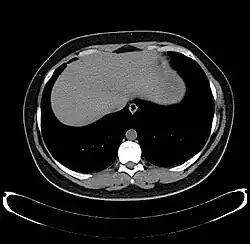

-

Axial CT image showing anomalous hepatic veins coursing on the liver's subcapsular anterior surface[74] -

Maximum intensity projection (MIP) CT image as viewed anteriorly showing the anomalous hepatic veins coursing on the anterior surface of the liver -